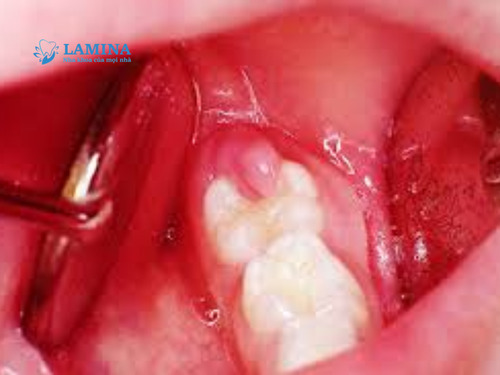

3. Sót chân răng hoặc mảnh xương

Trong một số trường hợp khó, mảnh xương hoặc chân răng nhỏ bị sót lại sẽ cọ xát mô nướu, gây viêm và đau âm ỉ suốt thời gian dài.